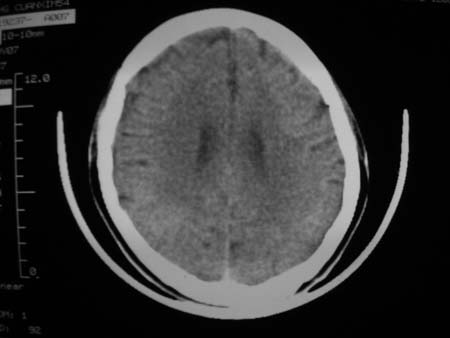

男,54岁,十天前被钢管打伤头顶部,现自述头部不适,视物模糊,并于两天前发觉右枕部有包块,既往未有明显异常.

颅骨多处骨质不完整,内板变薄,右侧额颞部局部呈“穿凿样”骨质缺损,相应区硬膜外密度略增高。多考虑:骨嗜酸性肉芽肿!

颅骨多处骨质不完整,内板变薄,右侧额颞部局部呈“穿凿样”骨质缺损,相应区硬膜外密度略增高。多考虑:骨髓瘤或骨嗜酸性肉芽肿!

颅骨多处骨质不完整,内板变薄,右侧额颞部局部呈“穿凿样”骨质缺损,缺损骨质边缘锐利无硬化,相应区硬膜外密度略增高。多考虑:骨嗜酸性肉芽肿!

颅骨多处骨质不完整,内板变薄,右侧额颞部局部呈“穿凿样”骨质缺损,相应区硬膜外密度略增高。多考虑:骨髓瘤或骨嗜酸性肉芽肿!10天前受伤,不会在2天前才发现头部包块,估计与外伤无关.